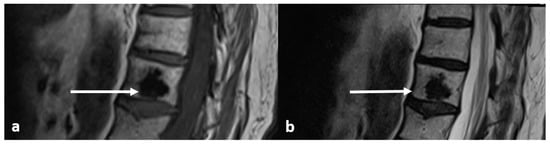

| Osteoid osteoma | Lucent nidus, usually 2–10 mm. May be surrounded by sclerotic rim. | Surrounding marrow oedema on fluid sensitive sequences (best seen on STIR). Nidus can be occult on MRI. |

| Osteoblastoma | Expansile lucent lesion. Sclerotic rim. Bone destruction. Variable intralesional ossification. | Low to intermediate T1 signal and intermediate to high T2 signal. Surrounding soft tissue oedema, extra osseous soft tissue component. |